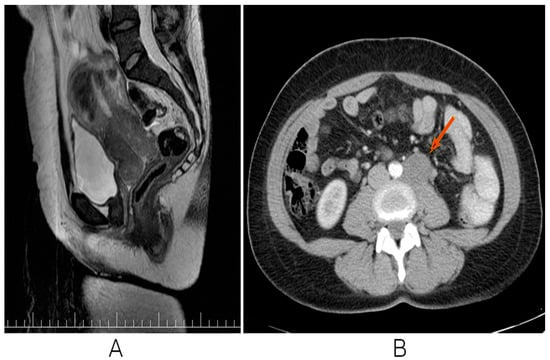

2.2. Imaging, Treatment Strategies, and Response